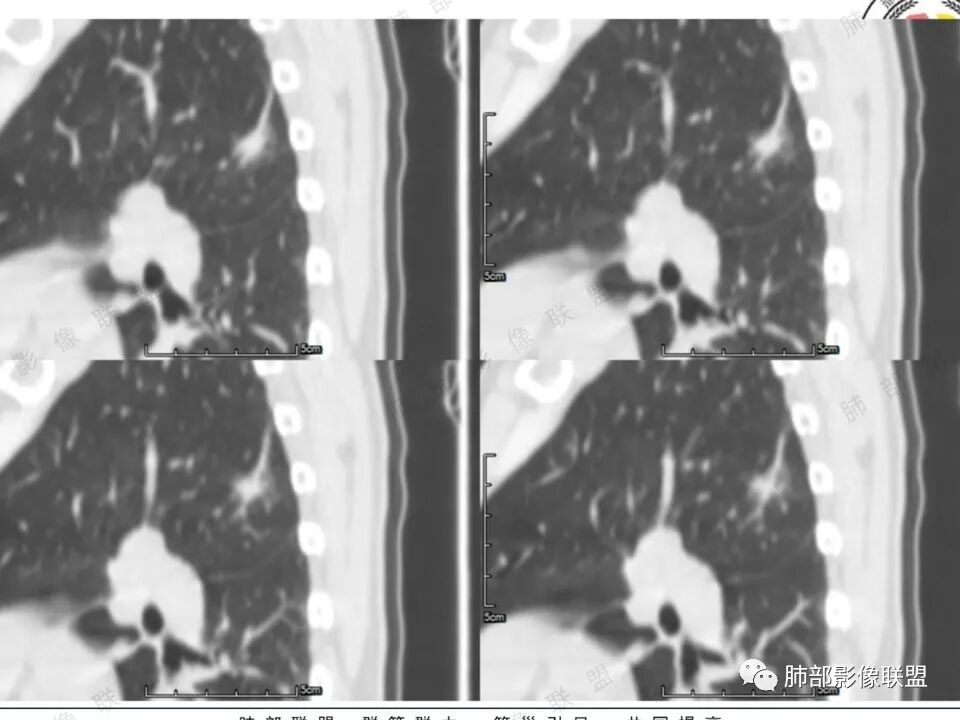

左肺上叶长条状病灶,胸膜牵拉,边缘平直,磨玻璃边界清楚,不均匀强化,考虑炎性,不完全排除肺癌

左肺上叶尖后段病灶,毛玻璃边界不清,实性成分边缘平直,重建,病灶长条形,增强明显强化,考虑炎症

中年女性,左肺上叶长条状病灶,宽基底与胸膜交界,胸膜凹陷,病灶边缘平直,局部收缩及膨隆,周围可见磨玻璃,其边界清楚,增强病灶不均匀强化,影像表现有炎性病变,也有明显占位表现,考虑OP,有膨胀性表现的小结节,不完全排除肺癌!需要结合相关检查。

女,41岁,体检发现肺部结节。左肺上叶长形病灶,具有轻度膨胧感,刀切尖角征,胸膜粘连,早期强化见薄环强化征象,后期有延迟强化特点。病灶周围不是很干净。考虑结核肉芽肿或炎症肉芽肿。

中年女性,体检发现。左肺上叶后段不规则结节灶,密度不均匀,病灶周围可以边界似清非清毛玻璃影,临近胸膜牵拉,增强扫描病灶明显不均匀强化。考虑炎性假瘤,鉴别腺癌。

患者中年女性,体检发现。胸部CT:左肺上叶后段长条形结节灶,边缘光滑,边界清楚,见分叶、毛刺、胸膜牵拉及平直征象。增强明显强化,内可见血管增粗,综合考虑恶性病变,浸润性腺癌可能大,鉴别结核。

左肺上叶后段条片状影,边缘部分模糊,前缘平直后缘澎隆,周围可见大部分清晰的GGO,毛刺不明显,可见索条影,内密度不均可见条状低密度,增强除条状低密度外明显强化。支气管似见病灶边缘截断。考虑腺癌可能,抗炎治疗除外炎性肉芽肿。

1.中年女性,体检发现;2.左肺上叶后段长条形结节灶,边缘有膨隆,也有收缩,腺癌和炎性结节都可以,但是周围见边界清楚磨玻璃影强烈提示腺癌可能性。3.显著强化的肺结节,无论如何都应当引起我们的高度重视!尽管炎性病灶和新生物都可以,尽管强化程度不能作为诊断癌肿的依据。